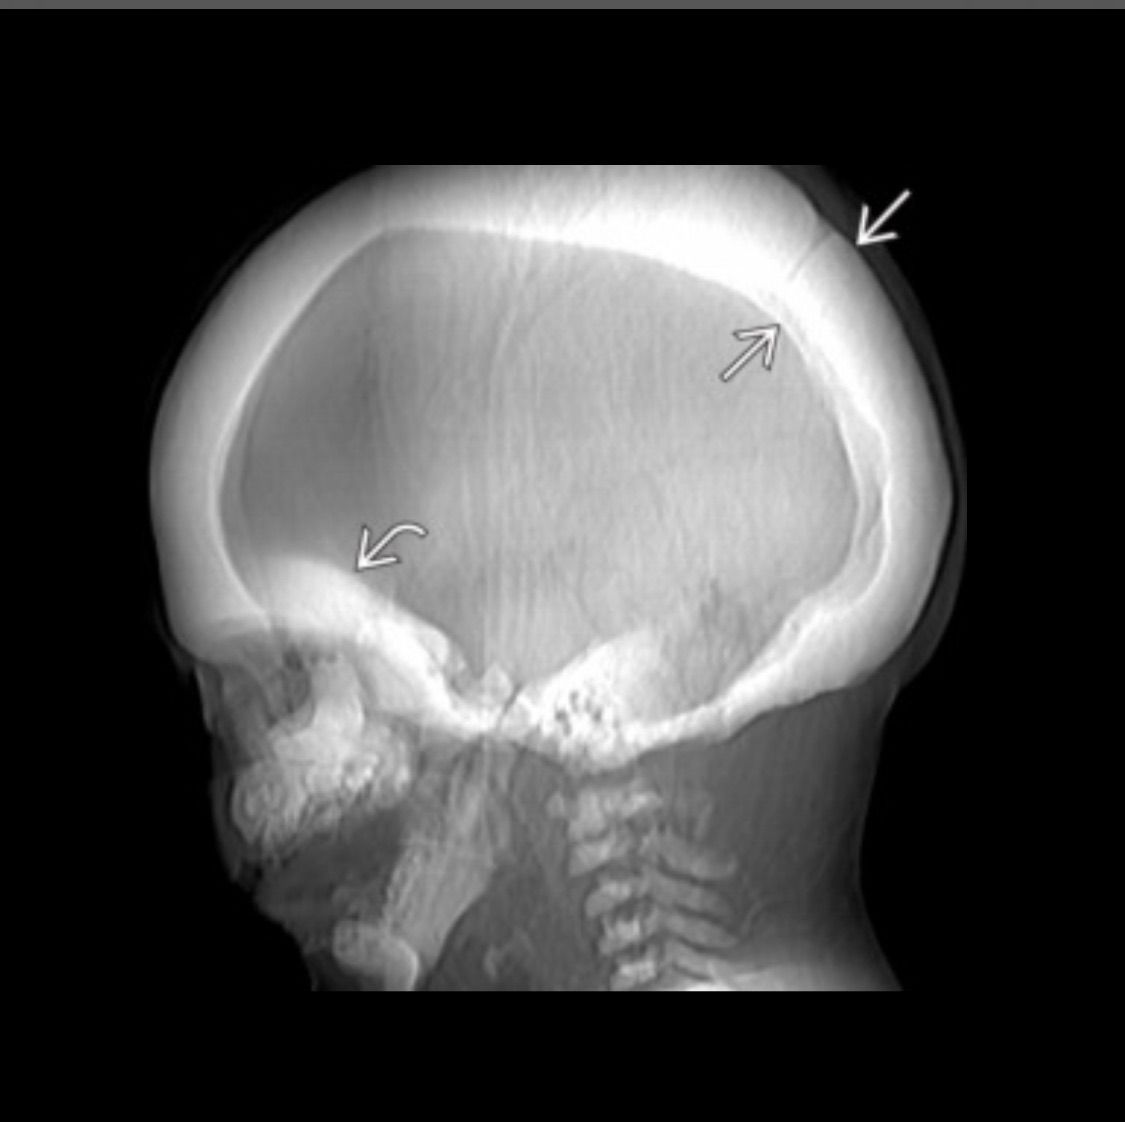

Albers Schönberg disease? Stone bone/ marble bone disease, characterized by sclerosis , mainly involving spline , pelvis abd skull base paradoxical fragility of bones. Due to mutation of CLCN7 gene.